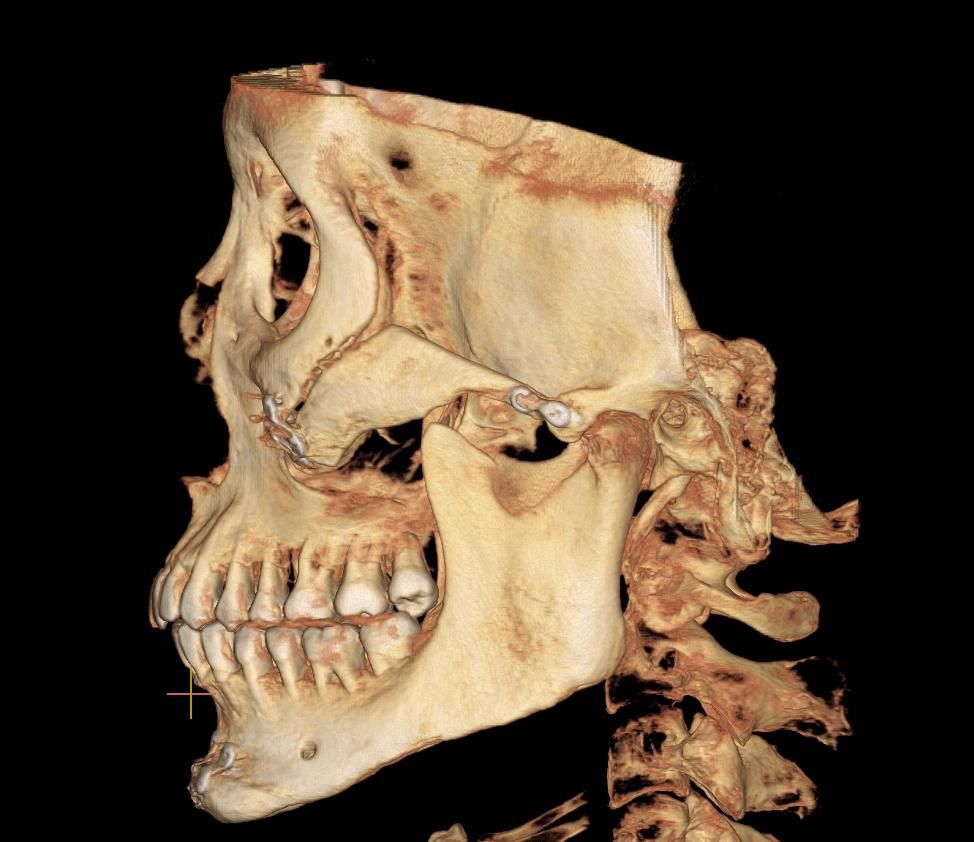

저 광대뼈 불유합이죠?ㅋㅋㅋㅋㅋㅋ

아니 제가 광대뼈 축소술 한지 이제 86일차인데 뼈가 아직도 안붙었어요 ㅋㅋ통증도 아직도 있고 근데 병원에서는 계속 뼈가 잘 붙는중이래요 ㅋㅋㅋㅋㅋㅋㅋ아니 의사님들 지금 제가 뼈가 잘붙고 있는걸로 보이나요??ㅋㅋㅋㅋ일상생활도 지금 못하고 있고 하 ㅋㅋㅋㅋ86일째인데 아직도 저렇게 조금 벌어져있는거 정상이에요? 성형외과 못믿으니까 정형외과 의사분들께 여쭤봅니다 하 ㅋㅋㅋ개월 수 말고 도대체 몇일째까지 기다려야 하는거에요?? 불유합 판정되려면?ㅋㅋㅋㅋㅋㅋㅋㅋㅋ아니 너무 화나네..진짜 솔직하게 말해줘요. 너무 늦으면 안되니까 그냥 불유합인 것 같으면 바로 병원가서 그냥 티타늄 박고 재수술하고 일상생활하게...ㅋㅋ

• 2번 째 사진